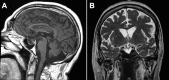

Pericardial effusion has a broad spectrum of clinical presentation, ranging from an incidental finding on imaging to a potentially fatal emergency such as pericardial tamponade, the most severe presentation. The authors present a case of a middle-aged male hospitalized due to shortness of breath. Initial work-up was positive for massive pericardial effusion with haemodynamic compromise. Additional study revealed panhypopituitarism. The acromegalic phenotype was suggestive of acromegaly secondary to pituitary adenoma, which had probably evolved to apoplexy. Hormone replacement was started with clinical improvement. At the 3-year follow-up, there was no evidence of recurrence of pericardial effusion. Panhypopituitarism is a relatively rare entity, but can lead to life-threatening complications such as adrenal crisis, coma and myxoedema-associated cardiac failure. Pericardial effusion is an extremely rare manifestation of secondary hypothyroidism.